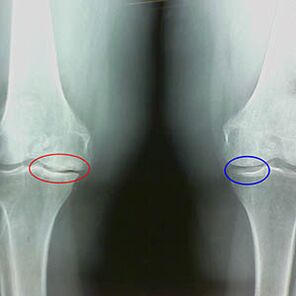

Die Bestimmung des Osteoarthritis erfolgt durch X -StrahlenAufdeckung der Teilnahme am pathologischen Prozess von Knochenstrukturen. Seine Veränderung zeigt, dass das Muskelsystem seit 5 bis 10 Jahren ein Ungleichgewicht hat. In der Regel Menschen Dolores Dolores Erfahrung seit mehreren Jahren.

In der ersten Stufe der Arthrose, was versehentlich erkannt wird, es gibt einen leichten Anstieg der Knochensporen. Wachstum tritt in Orten der höchsten Artikulationsinstabilität auf. Im Allgemeinen haben Patienten während der Bewegung selten Schmerzen oder Beschwerden.

Die zweite Stufe der Arthrose gilt als einfach. Die Radiographie zeigt signifikante Knochenbefehle, der Knorpel ist jedoch nicht betroffen. Die Menge an Synovialflüssigkeit ist verringert, aber die Schmerzsymptome treten nach einem langen Spaziergang und Rasse, Steifheit im Gelenk und Schmerzen beim Falten und in den Knien auf.

Anfangsmerkmale des X -Strahls der zweiten Stufe der Arthrose des Knies:

- die spitzen Kanten der interzeptiven Knollen in der Tibia, wo das Band in Form eines Kreuzes verbunden ist;

- Verengung der artikulären Lücke auf der medialen Seite;

- Die spitzen Kanten der Knochen der Knochen auf den medialen Seiten, weniger häufig auf der Seite, abhängig von der Entwicklung des Valgo oder der Verformung des vielfältigen Gelenks.

Für die zweite Stufe in Larsen Die Verengung der artikulären Lücke in mehr als 50% ist charakteristischDies kann jedoch nur in der Dynamik oder im Vergleich mit einem anderen Gelenk verifiziert werden.

Die Radiographie zeigt das Vorhandensein von Osteophyten, eine Weltraumänderung zwischen femoralen und warmen Knochen, was auf den Verlust von Knorpel im Knie hinweist. Manchmal zeigt die X -Linie der Kniegelenke signifikante Knorpelverschleißschilder, aber Patienten haben keine signifikanten Schmerzen.Im Gegenteil, die Arthrose der ersten Stufe kann die Kniefunktion unterbrechenda ist die Ursache des Schmerzes hypotonische Muskeln.